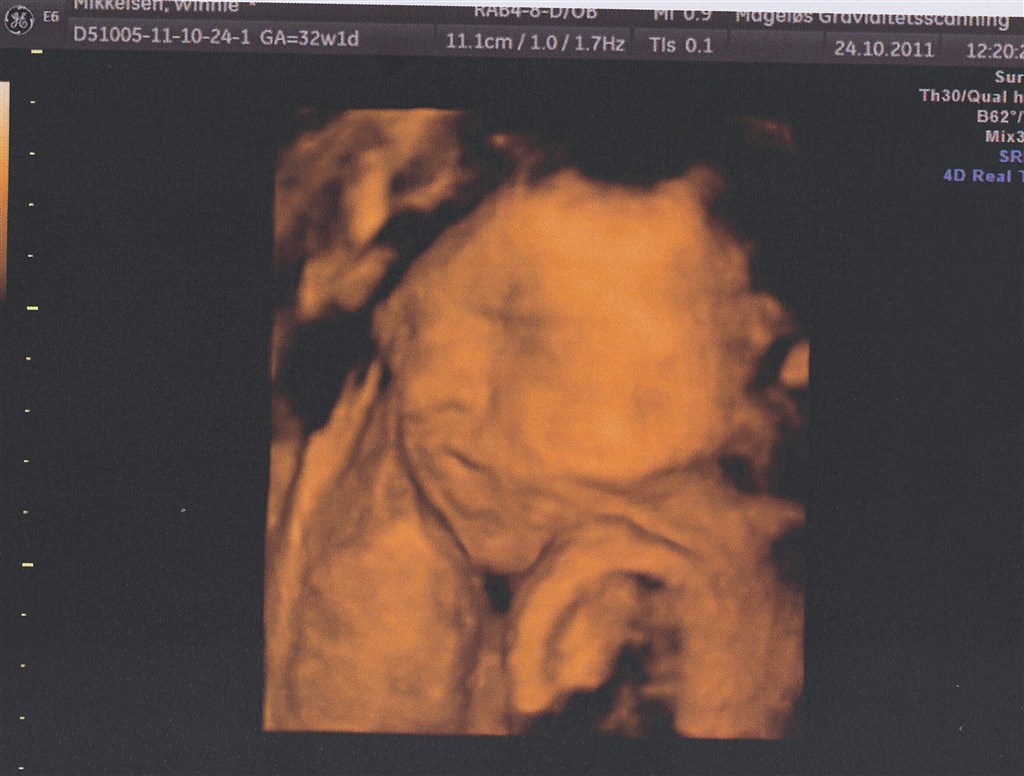

Selve 3D-scanningen gik dog lidt mere besværligt. Min moderkage ligger fortil (dog heldigvis højt), og lillepigen lå med hovedet vendt ind imod den. Jeg drak koldt vand og hoppede lidt, men det hjalp ikke meget.

Da jeg kom tilbage havde hun vendt hovedet lidt - stadig ikke ideelt men nok til at vi kunne få lidt billeder halvt i profil.

Det var sjovt at se det lille ansigt med den lille nedadvendte mund (præcis som min storesøsters datter har) og de lange øjenvipper. Det vigtigste var dog at hun havde det godt derinde og at vi fik bekræftet at alt var ok

Vedhæftede fotos (klik for at se i fuld størrelse)